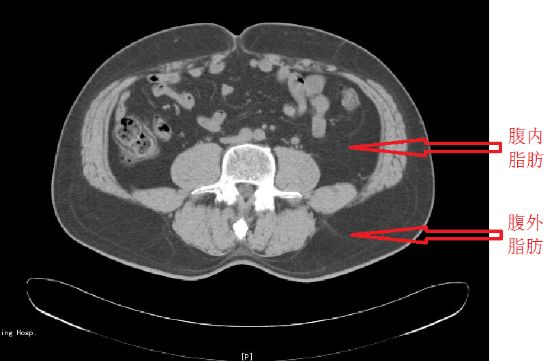

CT 或 MRI 技术:被认为是测量内脏脂肪的先进手段,是目前公认的测量内脏脂肪含量的金标准。

腹部脂肪的 CT 测量,要求病人在空腹状态下采用 CT 行腹部扫描(如下图)。当然,这种测试一般是用于科研,很少有人为了准确测量内脏脂肪跑去医院做CT 或 MRI检查吧。